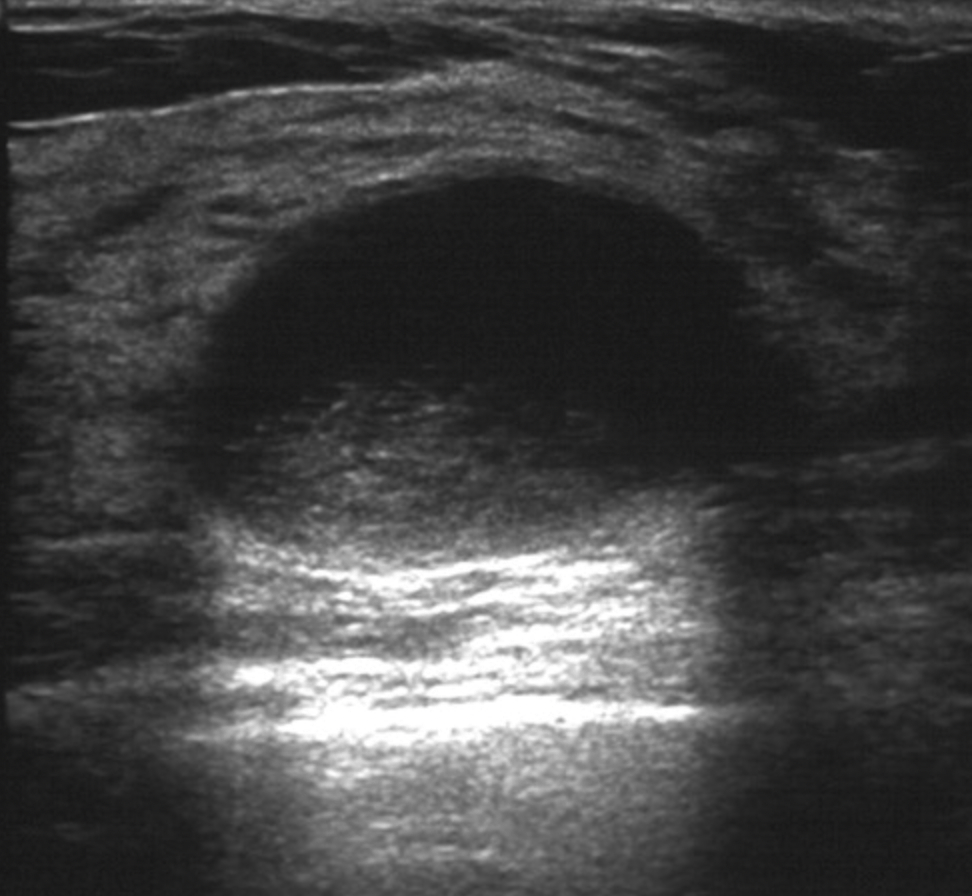

• Complicated cysts are defined by ultrasound criteria as:

• Lesions with homogeneous, low-level internal echoes:

• Due to echogenic debris:

• Without solid components, thick walls, or thick septa, and without vascular flow